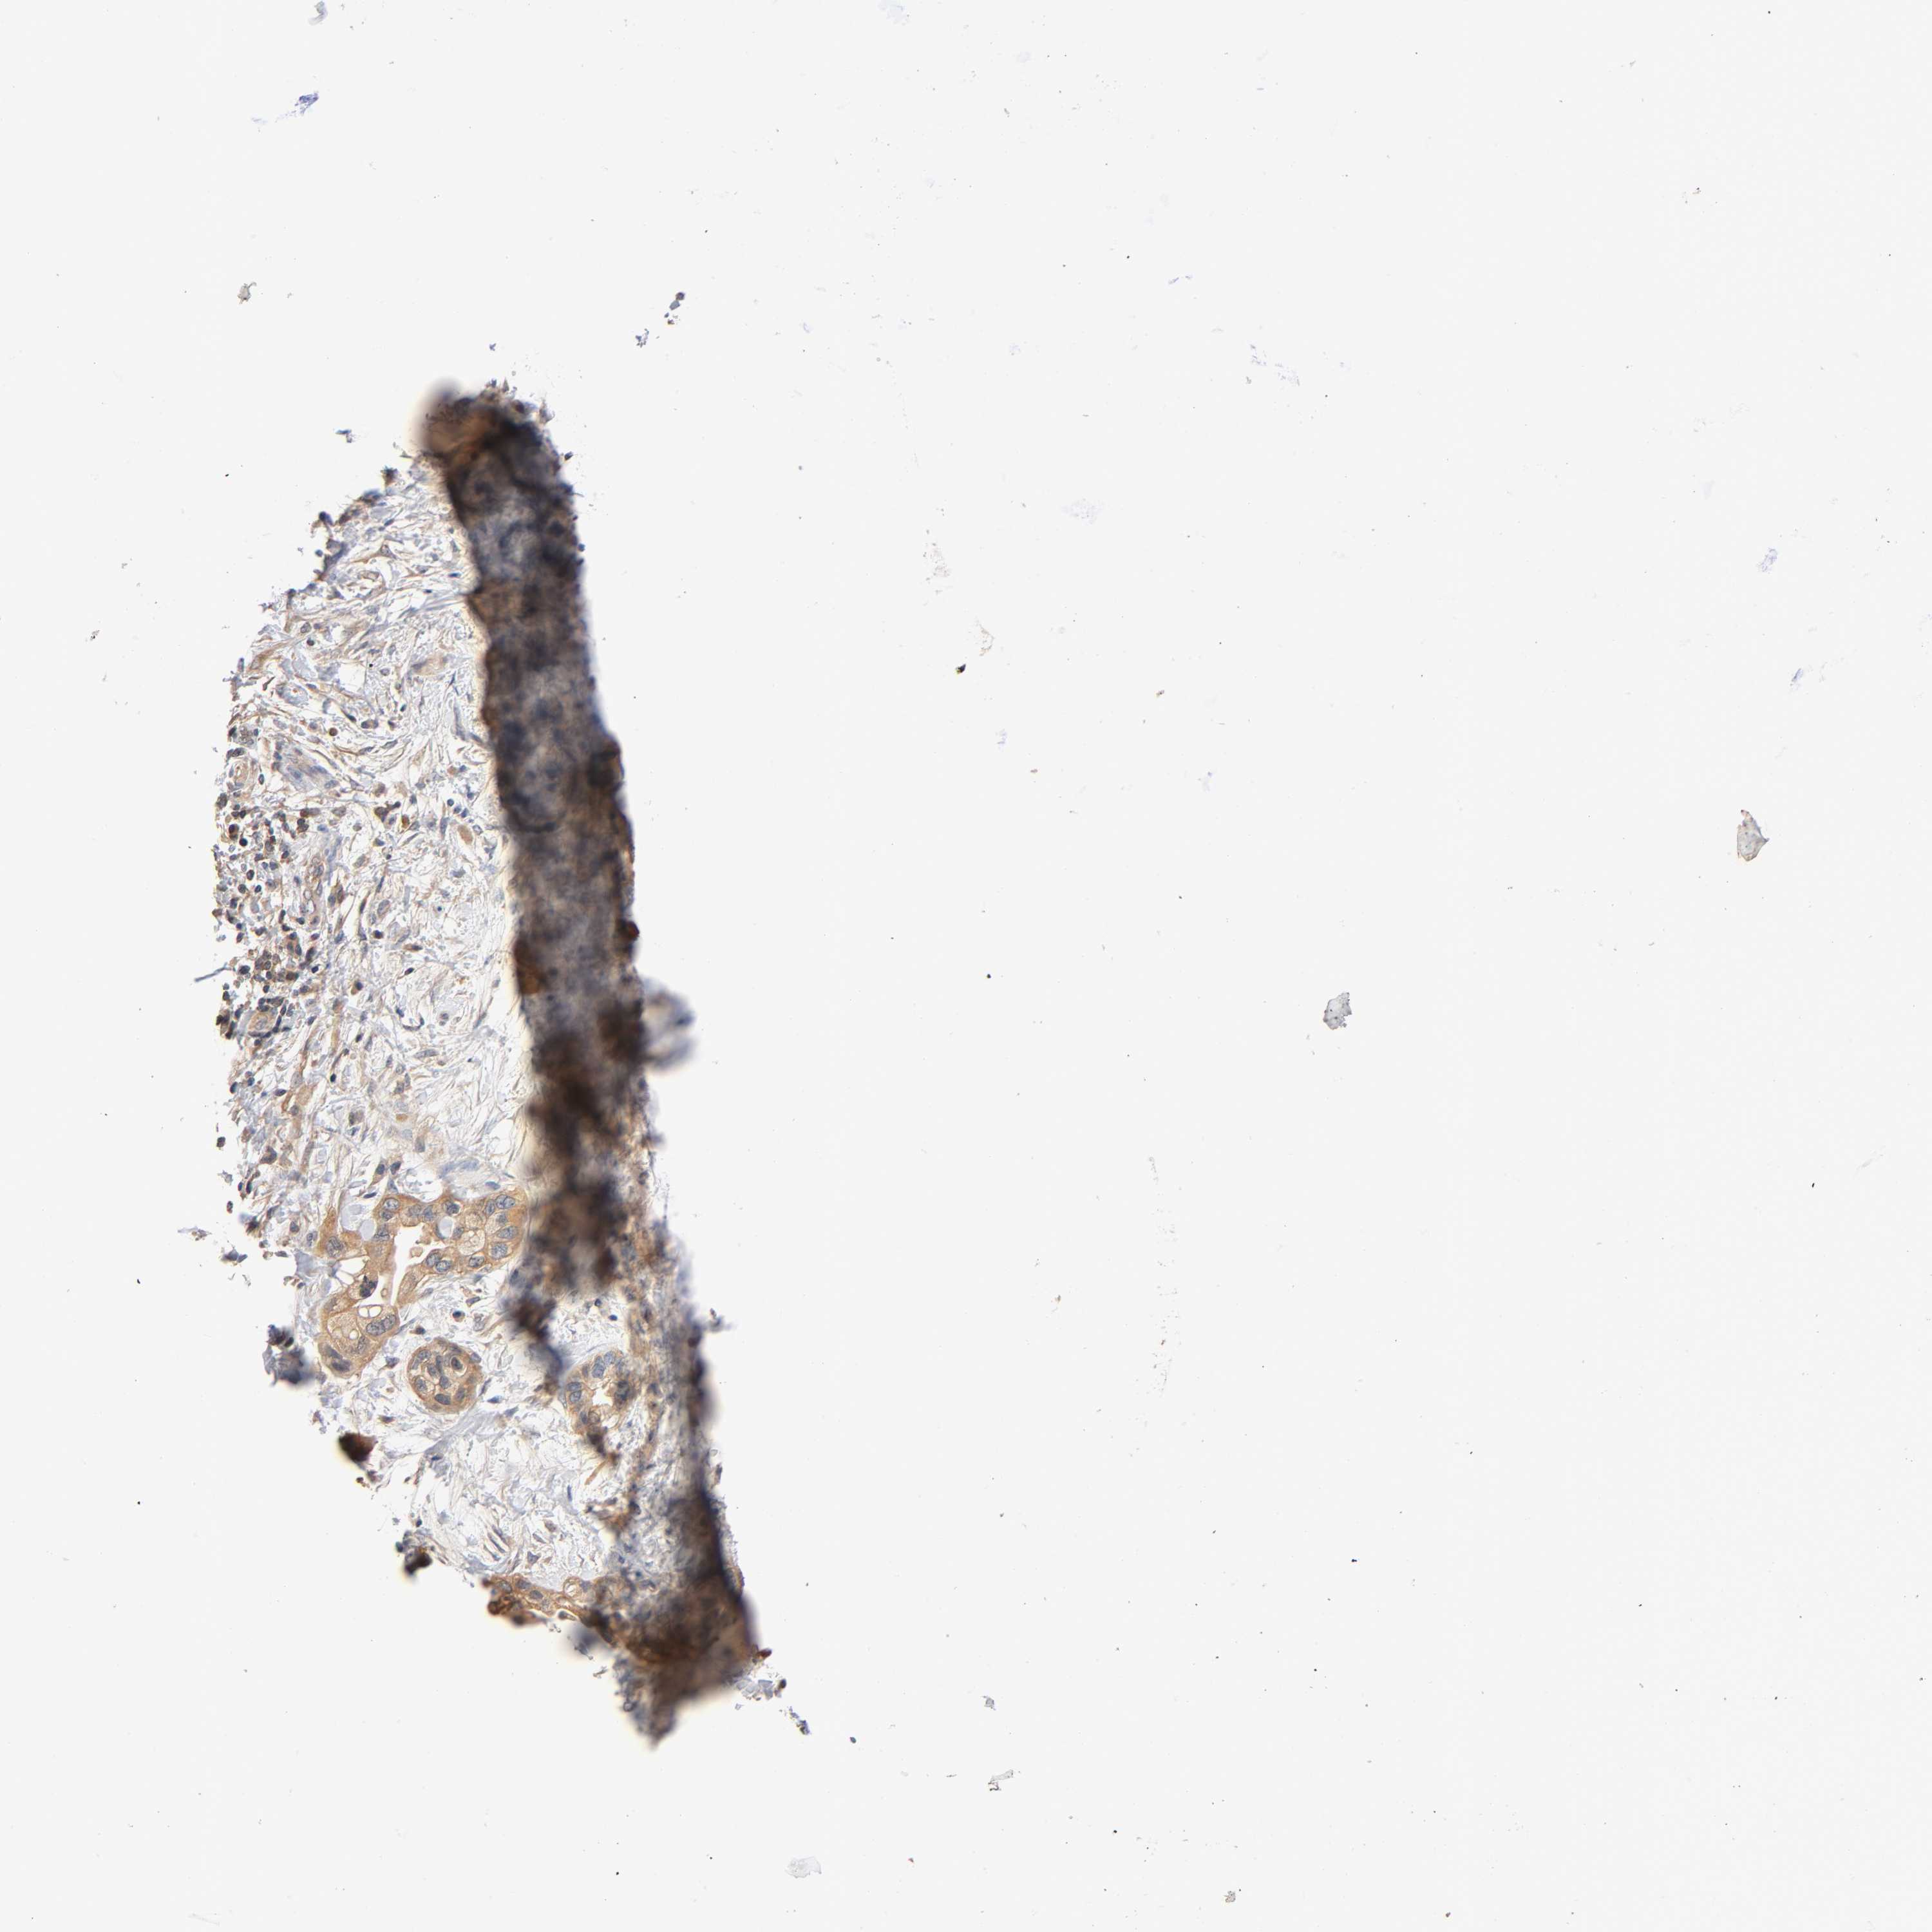

PANCREATIC CANCER - Protein expressioni

A mouse-over function shows sample information and annotation data. Click on an image to view it in a full screen mode. Samples can be filtered based on level of antibody staining by selecting one or several of the following categories: high, medium, low and not detected. The assay and annotation is described here.

Note that samples used for immunohistochemistry by the Human Protein Atlas do not correspond to samples in the TCGA dataset.

Antibody stainingi

Antibody staining in the annotated cell types in the current human tissue is reported as not detected, low, medium, or high, based on conventional immunohistochemistry profiling in selected tissues. This score is based on the combination of the staining intensity and fraction of stained cells.

Each image is clickable and will lead to virtual microscopy that enables deeper exploration of all samples and also displays staining intensity scores, fraction scores and subcellular localization as well as patient and tissue information for each sample.

Antibody HPA004177

Antibody CAB006252

Staining

High

Medium

Low

Not detected

Intensity

Strong

Moderate

Weak

Negative

Quantity

>75%

75%-25%

<25%

None

Location

Nuclear

Cytoplasmic/membranous

Cytoplasmic/membranous,nuclear

Adenocarcinoma, NOS

Adenocarcinoma, metastatic, NOS